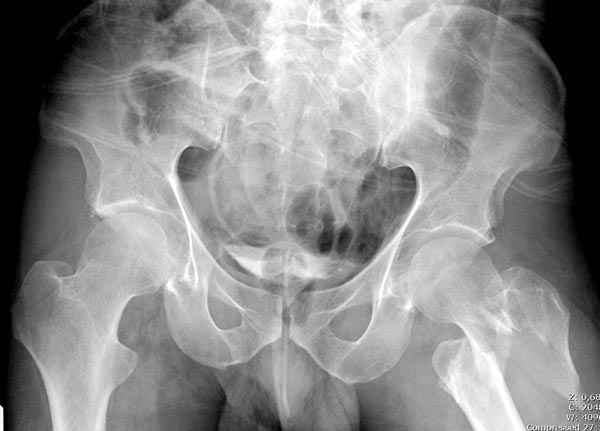

Предугадать распространение линий перелома при чрезвертельных и оскольчатых переломах трудно, поэтому для принятия правильного решения рекомендуется Компьютерно Томографические исследование.

При отсутствии КТ, снимок на вытяжении поможет увидеть общую картину расположения отломков, особенно потенциальные места введения импланта. Риск раскола в этом случае огромный, поэтому больной должен быть дообследован.

Здесь пара похожих случаев.